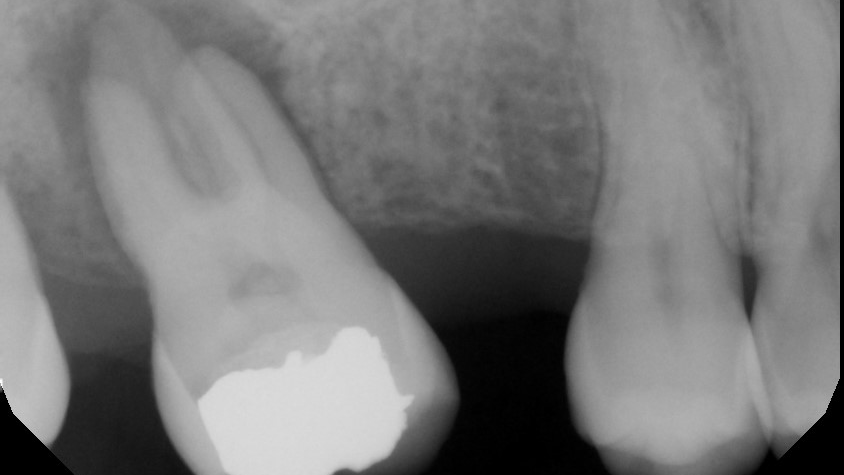

From www.radiodontics.com